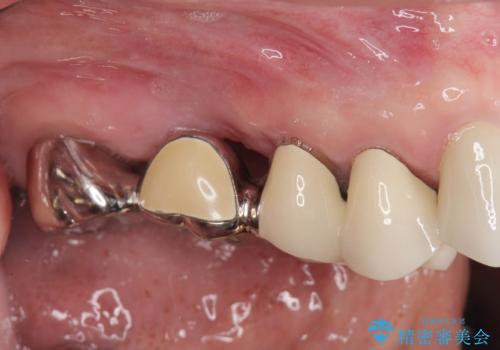

[ 破折し大きく吸収した歯槽骨 ] 他院では難しいと言われたインプラント治療

![[ 破折し大きく吸収した歯槽骨 ] 他院では難しいと言われたインプラント治療の症例 治療前](https://seimitsushinbi.jp/wp/wp-content/uploads/2024/10/073ce5e06775df372887a513b05b34d0-500x350.jpg?v=1729760111)

![[ 破折し大きく吸収した歯槽骨 ] 他院では難しいと言われたインプラント治療の症例 治療後](https://seimitsushinbi.jp/wp/wp-content/uploads/2024/10/7e00d9287463e80cbc3d4b87784b3d86-500x350.jpg?v=1729760167)